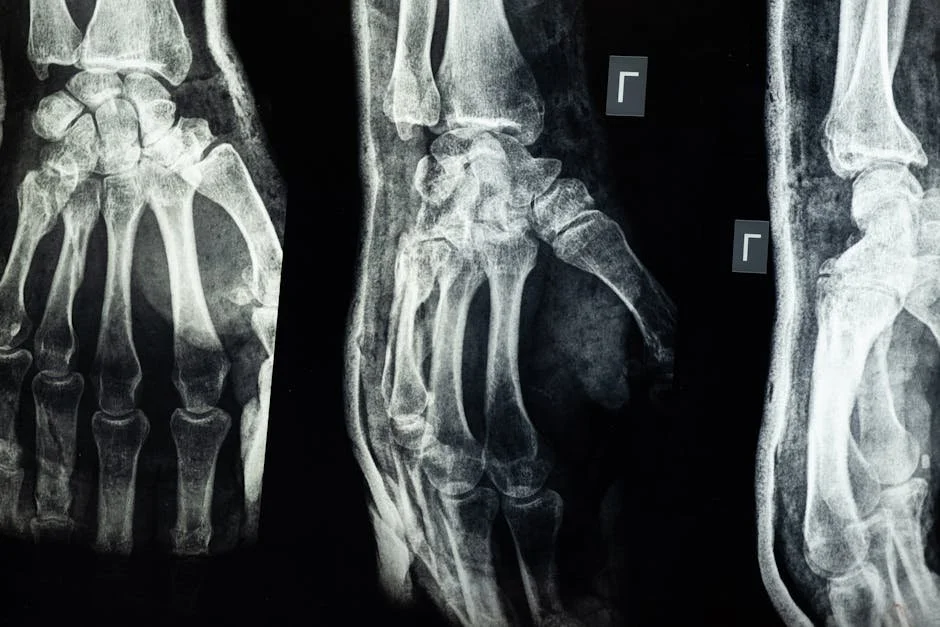

Imaging and Classification

• X-ray: first-line and usually enough

• CT: complex areas like spine or pelvis

• MRI: hidden fractures or soft-tissue damage

Fractures are labeled closed or open, displaced or non-displaced, complete or incomplete. Pattern words—transverse, oblique, spiral—tell us how the force acted on the bone. These details guide treatment and predict healing time. If you are comparing bone breaks with other injuries, our article on the Difference Between Sprains and Strains can help.